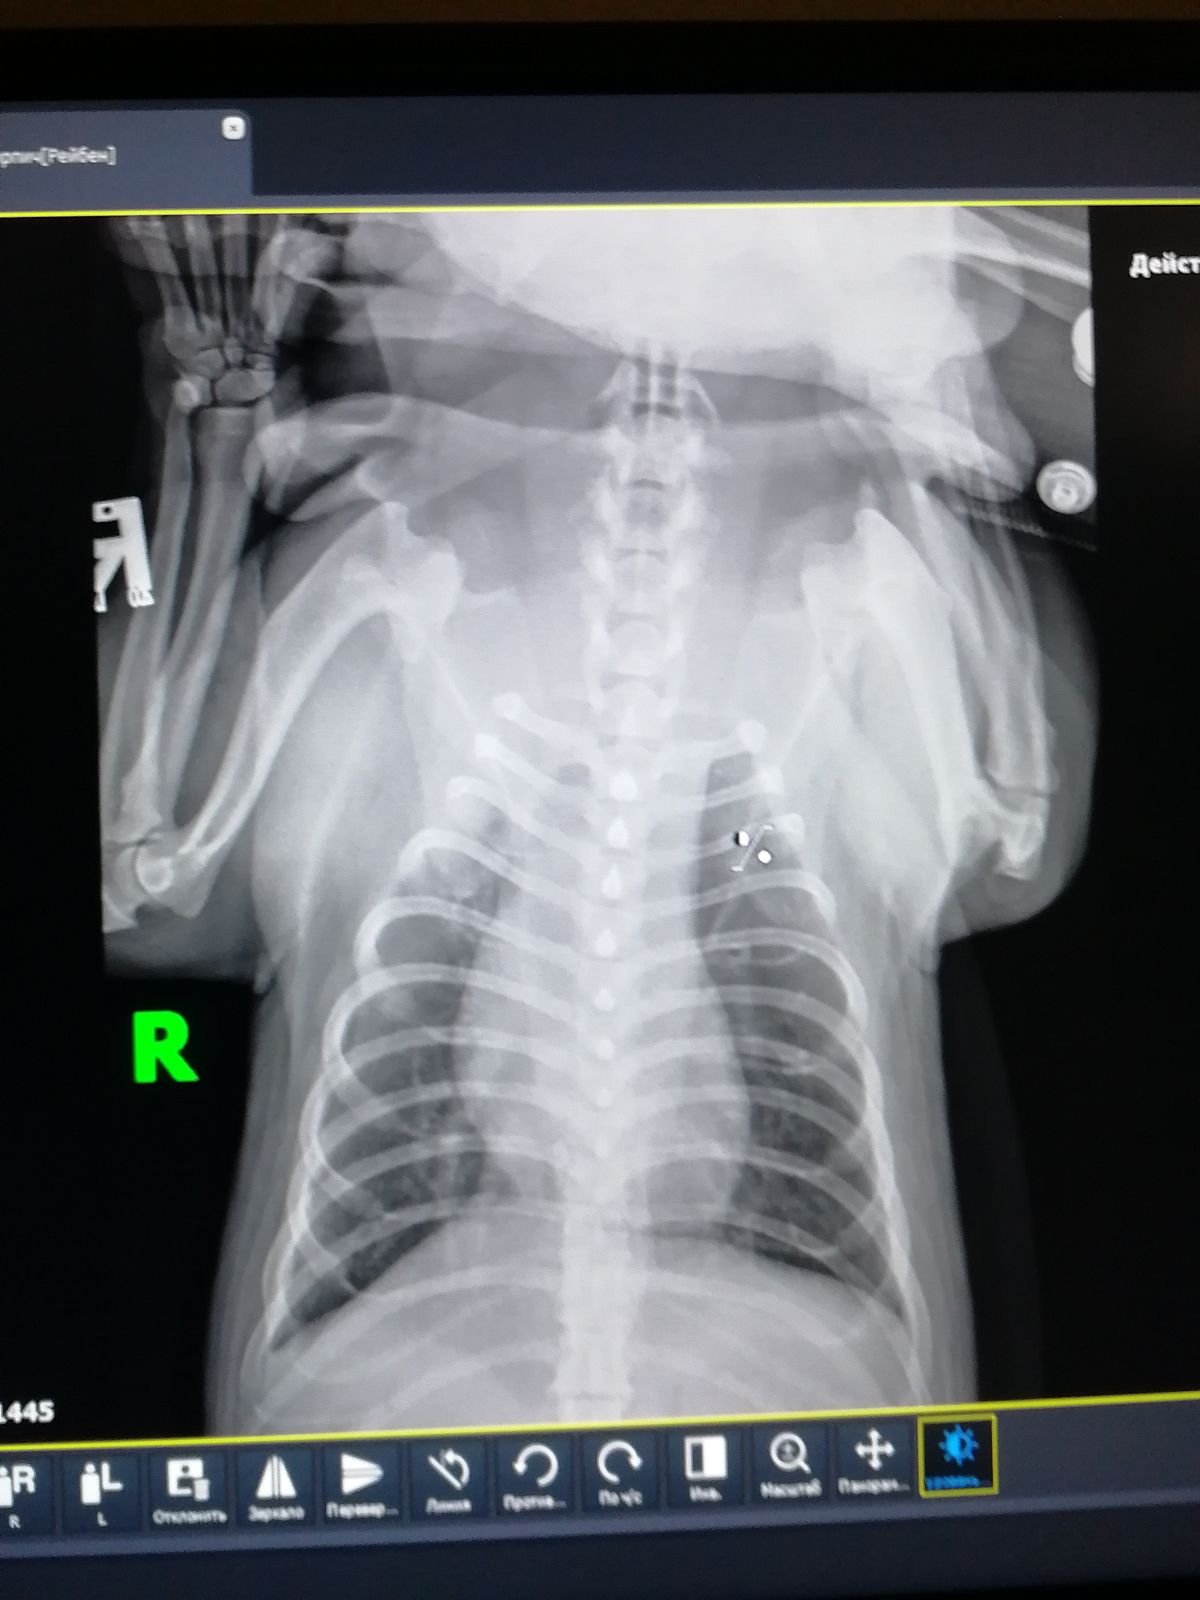

Вопрос ветеринарам по рентг. снимку собаки

Собака простужена, более 2х недель кашель. Вялый.

Подскажите, пожалуйста, на снимке Вы видете воспаление?

Сегодня сказали, что похоже на новообразование....Плачу...